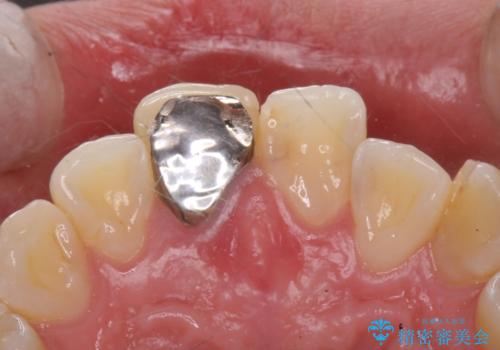

- 前歯のかぶせ物の色が気になるとのことで来院された患者様です。

セラミッククラウンで作り変えていきます。

- 右上1: 仮歯/11,000円、ジルコニアクラウン(スタンダード)/121,000円 合計132,000円(税込)費用は治療当時の料金となります